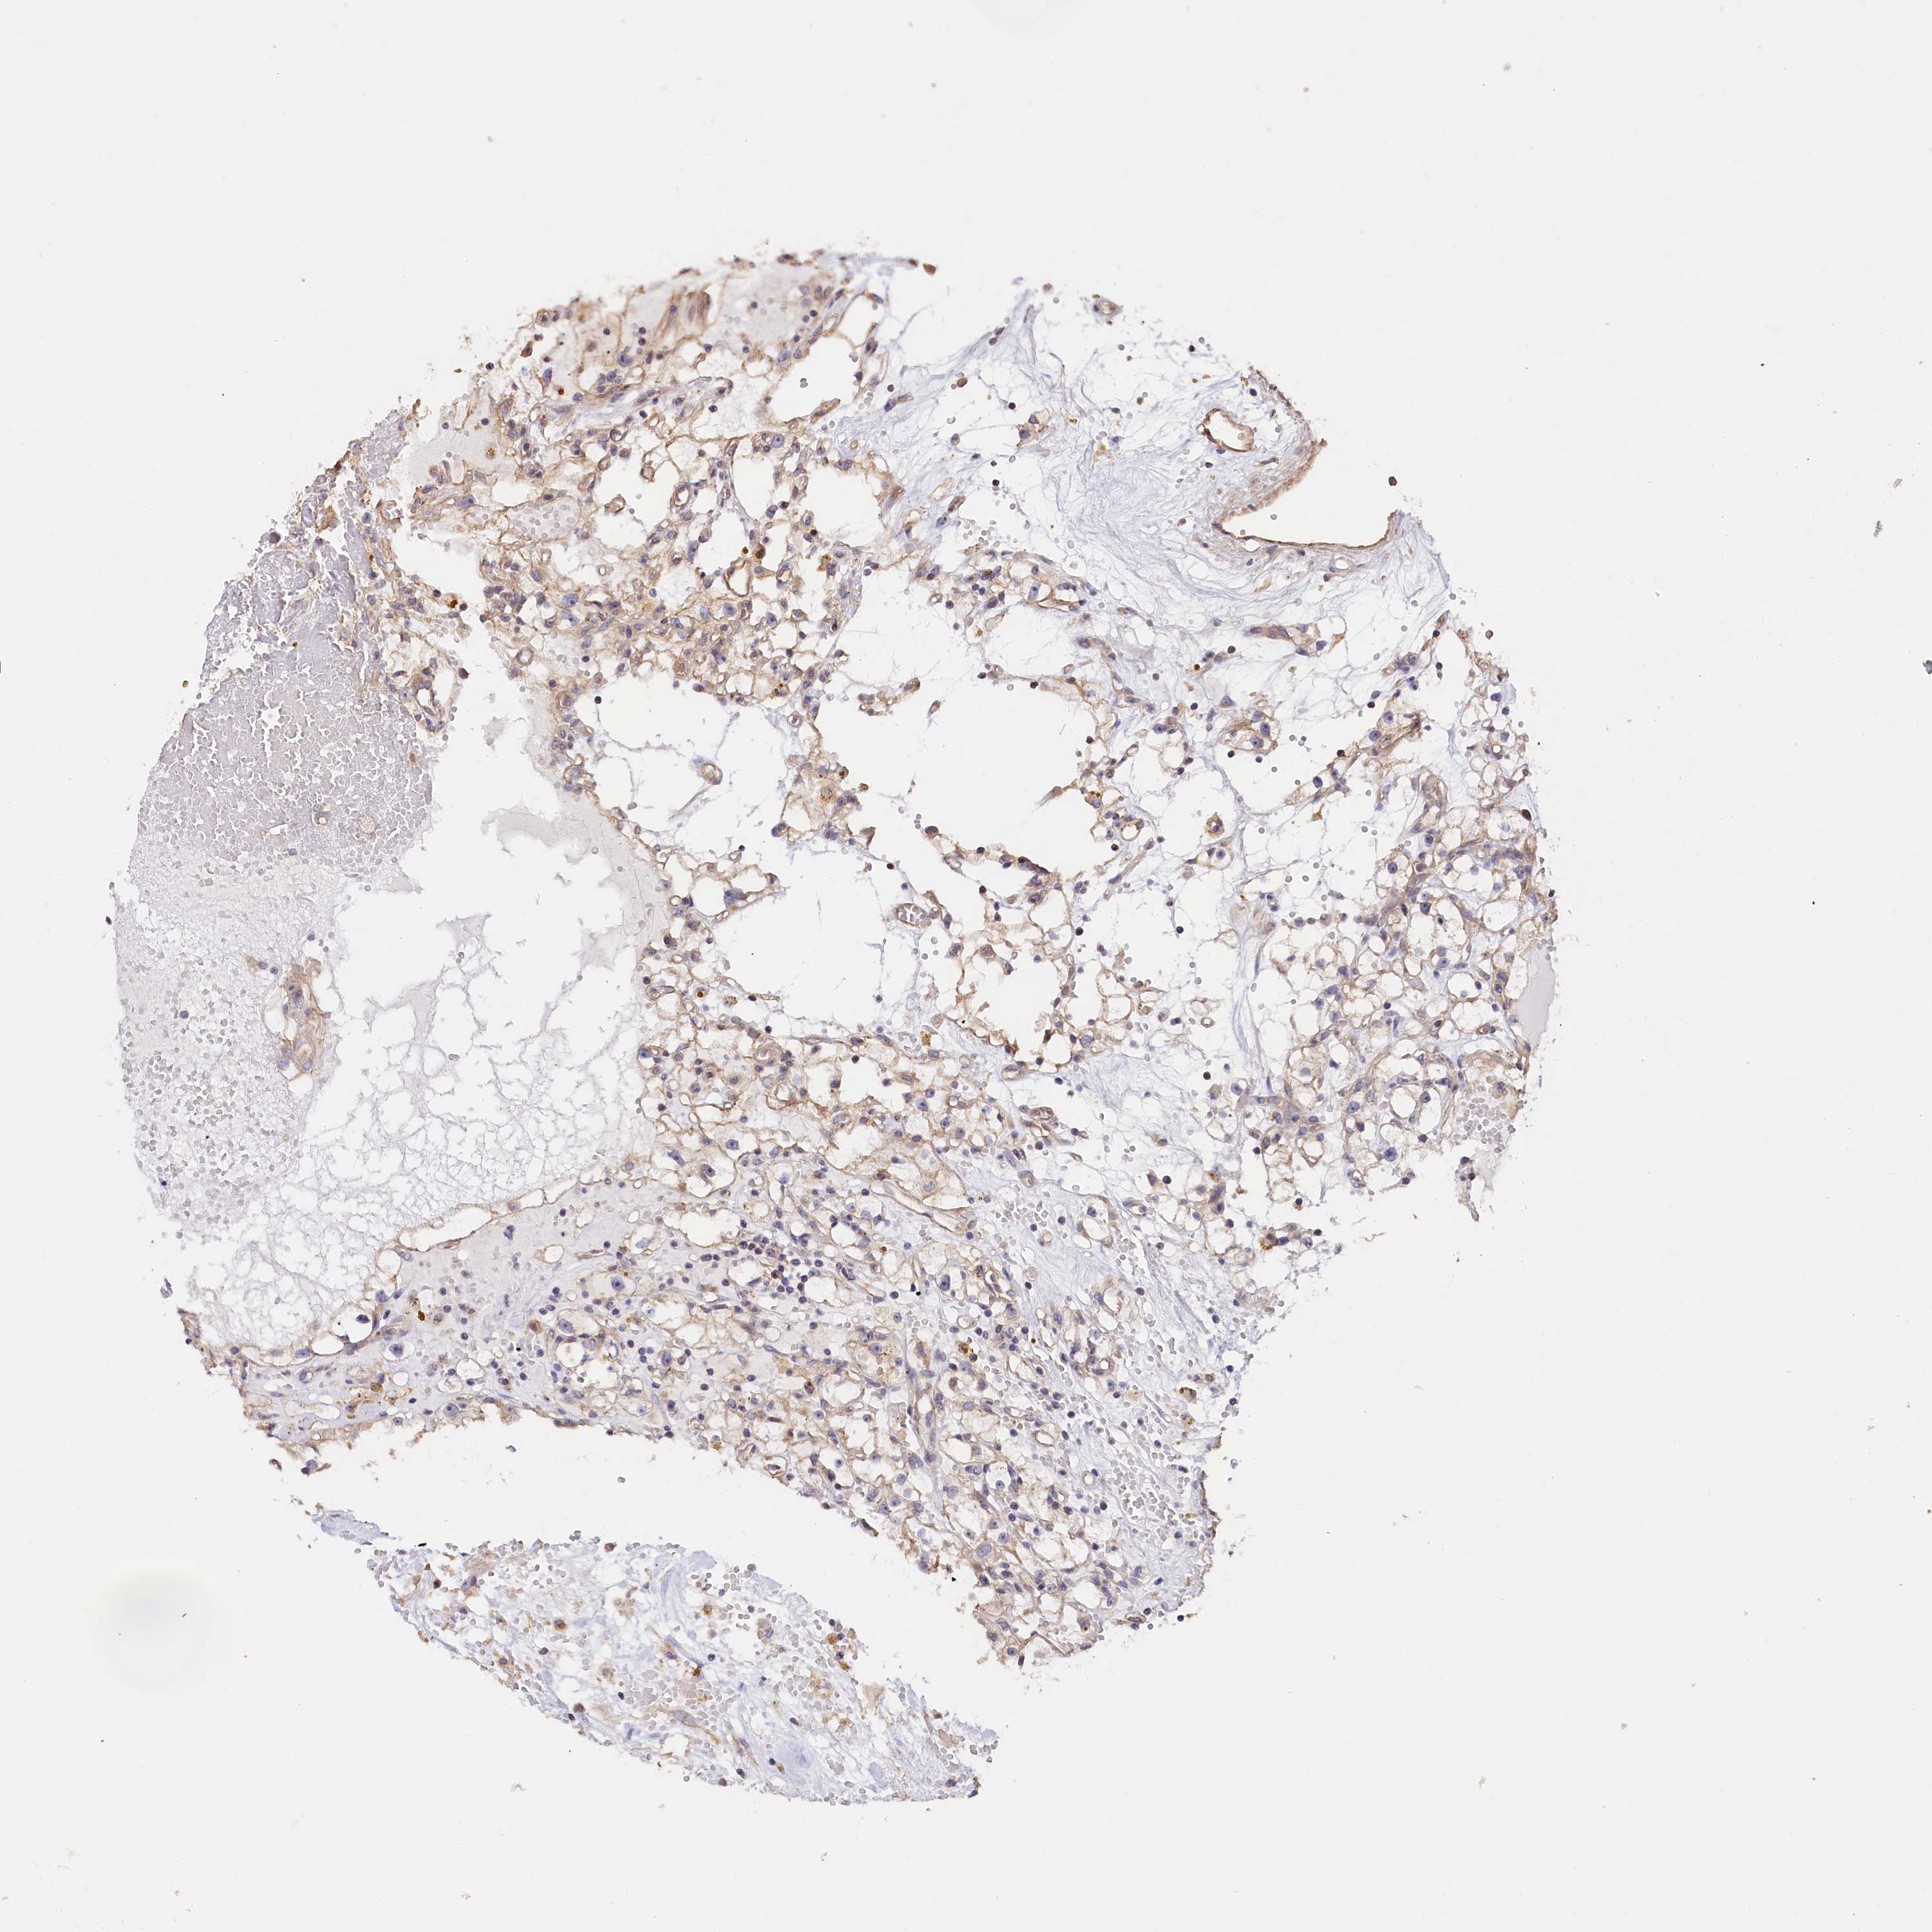

KIDNEY RENAL CLEAR CELL CARCINOMA (TCGA) - Interactive survival scatter ploti

The Survival Scatter plot shows the clinical status (i.e. dead or alive) for all individuals in the patient cohort, based on the same data that underlies the corresponding Kaplan-Meier plots. Patients that are alive at last time for follow-up are shown in blue and patients who have died during the study are shown in red.

The x-axis shows the expression levels (FPKM) of the investigated gene in the tumor tissue at the time of diagnosis. The y-axis shows the follow-up time after diagnosis (years). Both axes are complimented with kernel density curves demonstrating the data density over the axes. The top density plot shows the expression levels (FPKM) distribution among dead (red) and alive patients (blue). The right density plot shows the data density of the survived years of dead patients with high and low expression levels respectively, stratified using the cutoff indicated by the vertical dashed line through the Survival Scatter plot. This cutoff is automatically defined based on the FPKM cutoff that minimizes the p-score. The cutoff can be changed by dragging the vertical line or by entering a cutoff value in the square labeled "Current cut-off".

Under the Survival Scatter plot the p-score landscape (black curve; left axis) is shown together with dead median separation (red curve; right axis). Dead median separation is the difference in median mRNA expression between patients who have died with high and low expression, respectively. It is calculated as follows: median FPKM expression of dead patients with high expression - median FPKM expression of dead patients with low expression. This is intended to aid the user in visually exploring custom cutoffs and the associated p-scores and dead median separation.

Individual patient data is displayed and can be filtered by clicking on one or more of the category buttons on the top of the page. Categories describing expression level and patient information include: high, low, alive, dead, female, male and tumor stages. The scale of the x-axis can be toggled between linear and log-scale by clicking on the "x log" button. Mouse-over function shows TCGA ID, patient information and mRNA expression (FPKM) for each patient.

& Survival analysisi

Kaplan-Meier plots summarize results from analysis of correlation between mRNA expression level and patient survival. Patients were divided based on level of expression into one of the two groups "low" (under cut off) or "high" (over cut off). X-axis shows time for survival (years) and y-axis shows the probability of survival, where 1.0 corresponds to 100 percent.

KATNB1 is not prognostic in Kidney Renal Clear Cell Carcinoma (TCGA)

Best expression cut offi

Based on the FPKM value of each gene, patients were classified into two groups and association between prognosis (survival) and gene expression (FPKM) was examined. The best expression cut-off refers the FPKM value that yields maximal difference with regard to survival between the two groups at the lowest log-rank P-value. Best expression cut-off was selected based on survival analysis .

When clicking on this number, the vertical dashed line indicating cut-off, the interactive survival plot, and the Kaplan-Meier curve will be adjusted to show results based on the best expression cut-off.

: 13.77

Median expressioni

Median expression refers to the median FPKM value calculated based on the gene expression (FPKM) data from all patients in this dataset. When clicking on this number, the vertical dashed line indicating cut-off, the interactive survival plot, and the Kaplan-Meier curve will be adjusted to show results based on the median expression.

: N/A

Median follow up timei

Median follow up time refers to the median time (years) after diagnosis with this type of cancer, based on clinical data from all patients in this dataset.

P scorei

Log-rank P value for Kaplan-Meier plot showing results from analysis of correlation between mRNA expression level and patient survival.

N/A

5-year survival highi

5-year survival for patients with higher expression than the expression cutoff.

For melanoma and glioma, 3-year survival is shown.

5-year survival lowi

5-year survival for patients with lower expression than the expression cutoff.

TCGA RNA samplesi

RNA-seq data is reported as average FPKM (number Fragments Per Kilobase of exon per Million reads), generated by the The Cancer Genome Atlas (TCGA) .

Normal distribution across the dataset is visualized with box plots, shown as median and 25th and 75th percentiles. Points are displayed as outliers if they are above or below 1.5 times the interquartile range. FPKM values of the individual samples are presented next to the box plot.

Average pTPM 12.1

Number of samples 521